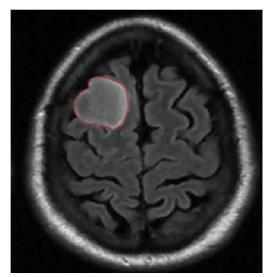

5.4 Results on brain MRI images

To achieve accurate segmentation of medical images, we have carefully tuned the parameters α, λ, and μ, which play a critical role in the performance of the DRLSE algorithm. These parameters control key aspects of the level set evolution, such as the smoothness of the contour (α), the fitting to the object boundaries (λ), and the regularization of the level set function (μ).

Using an empirical approach, we iteratively adjusted these values to obtain the best segmentation results for the images shown in Figure 10. Specifically, for brain MRIs, we found that setting α=0.5, λ=6, and μ=0.02 provided optimal segmentation results. These values effectively balance the trade-off between contour smoothness and accuracy in detecting object boundaries.

The segmentation process required several iterations to refine these parameters, highlighting the importance of adapting them to the specific characteristics of the images being analyzed. The results confirm the robustness of the DRLSE algorithm in delimiting structures in medical images.

Figure 10. Segmentation result. with the DRLSE algorithm